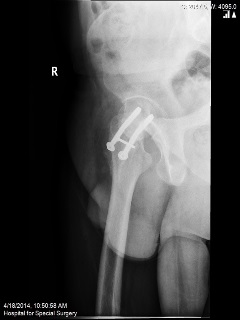

A 37-year-old athletic male underwent an open reduction and internal fixation (ORIF) of his right hip for a stress fracture sustained whilst running the New York Marathon. However, due to non-union of his fracture he underwent revision of the fixation with bone grafting. He presented with persistent pain in the right hip after 18 months from his second operation.

Plain radiographs were performed.

Q. What are your thoughts on the findings of the above radiographs?

The radiographs show non-union of the hip fractures.